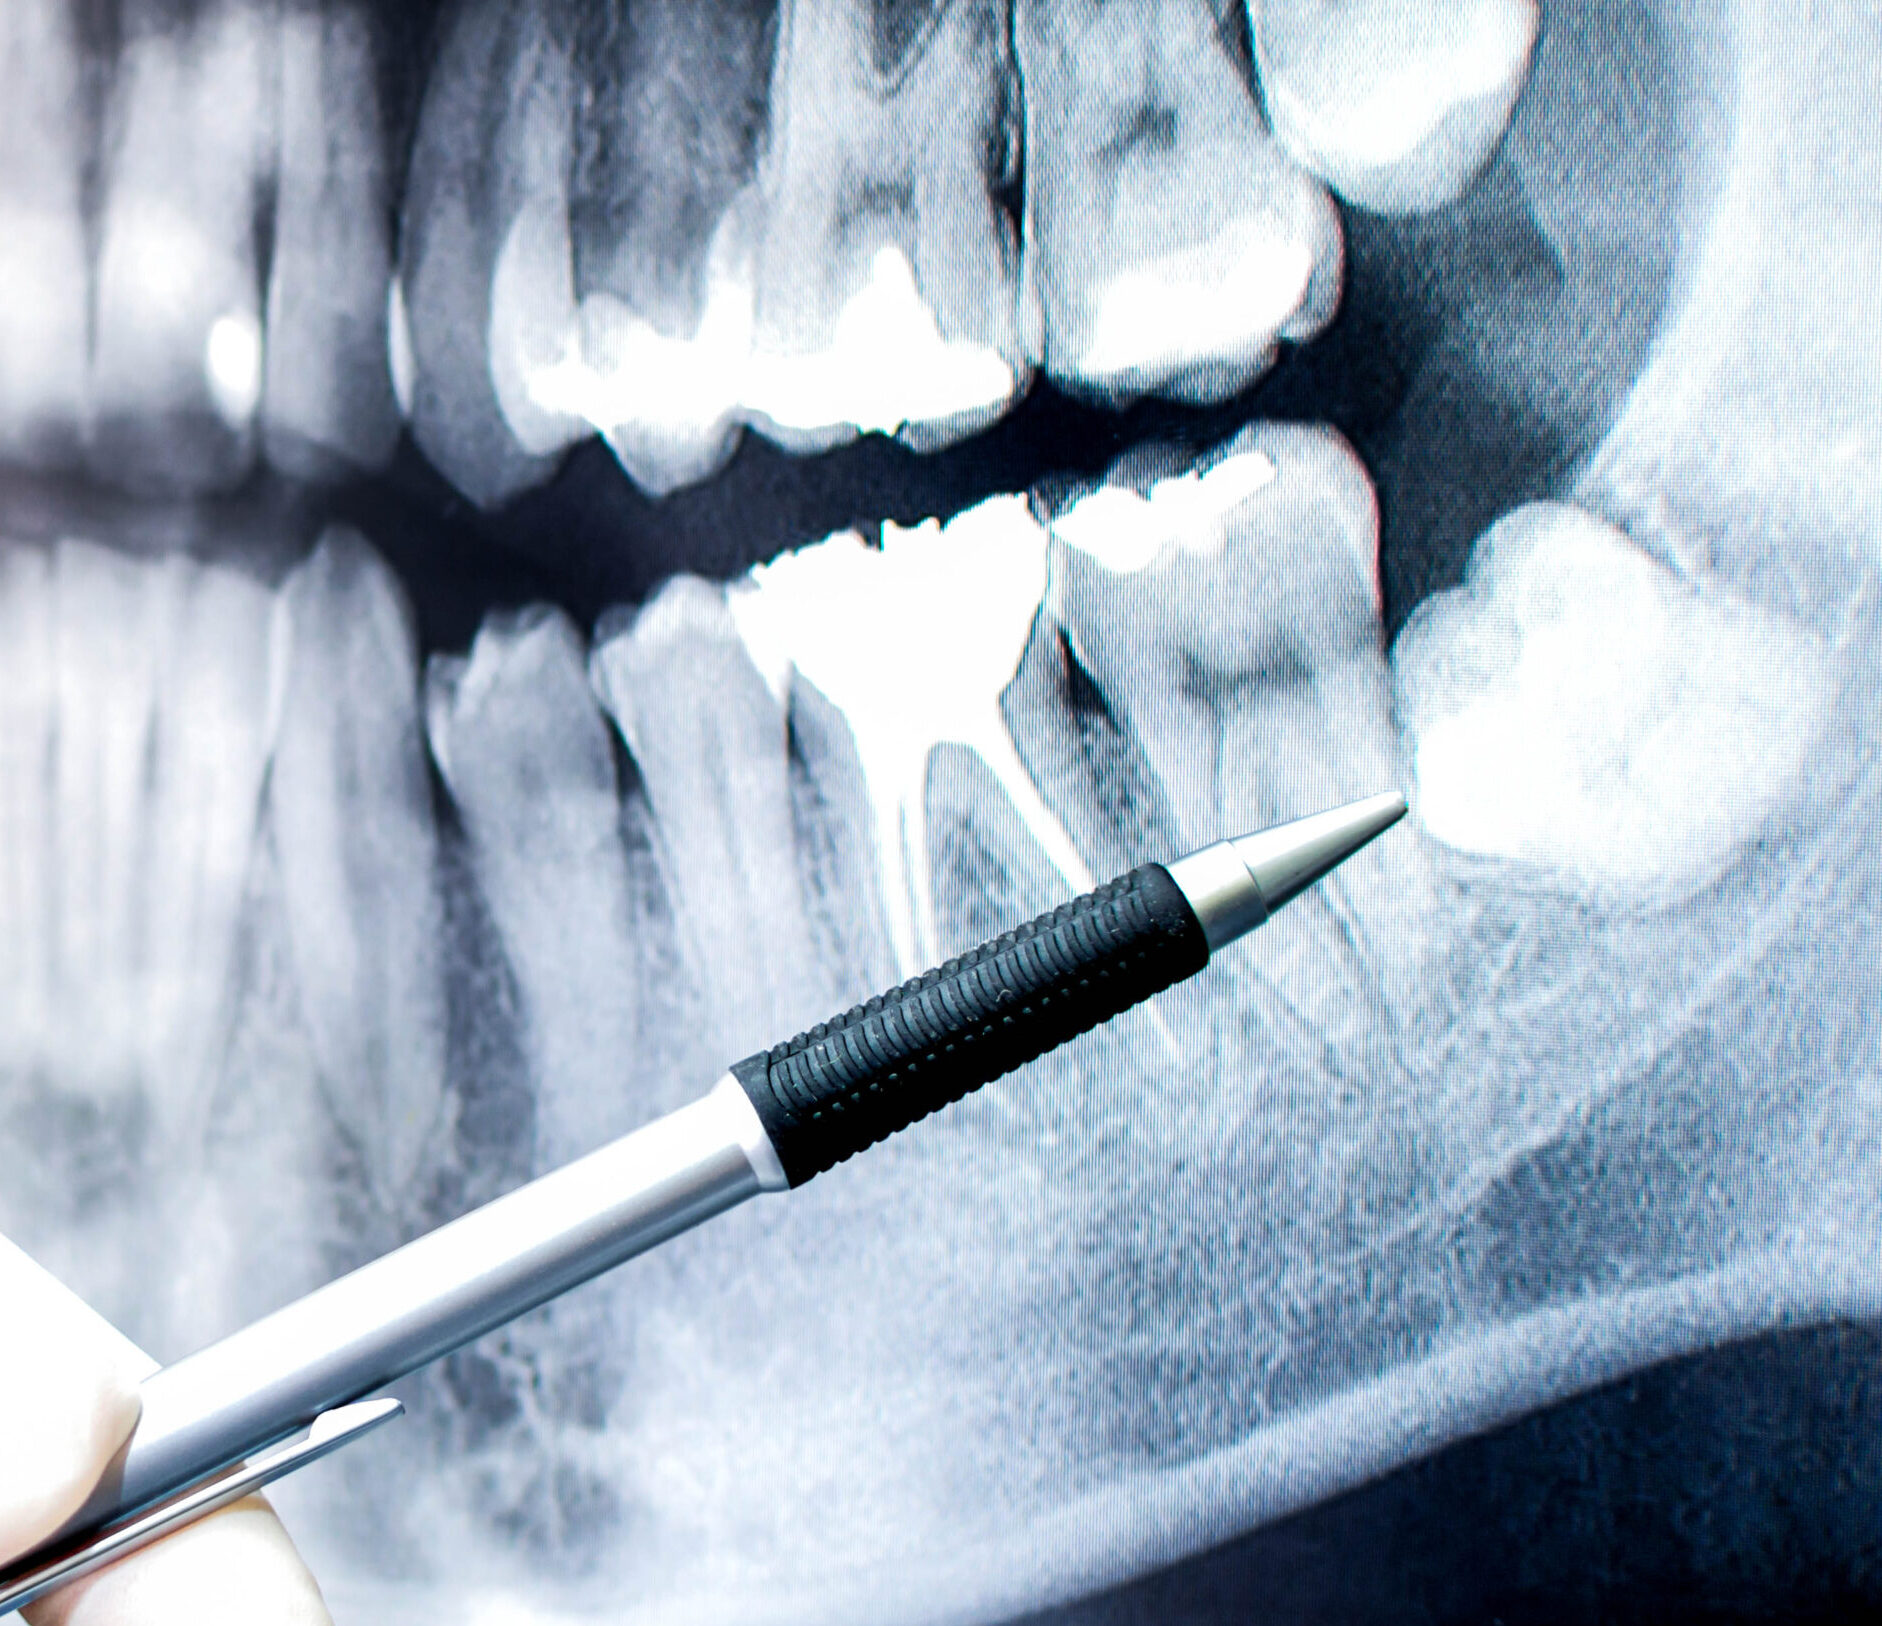

We use local anaesthetic to minimise discomfort and make sure you are relaxed and ready before we begin. We carefully remove your tooth by loosening it little by little until it is easily able to come out. In some cases, and if your wisdom tooth is impacted, we need to make a small cut in your gum to remove it successfully. We may also need to remove large teeth in parts.